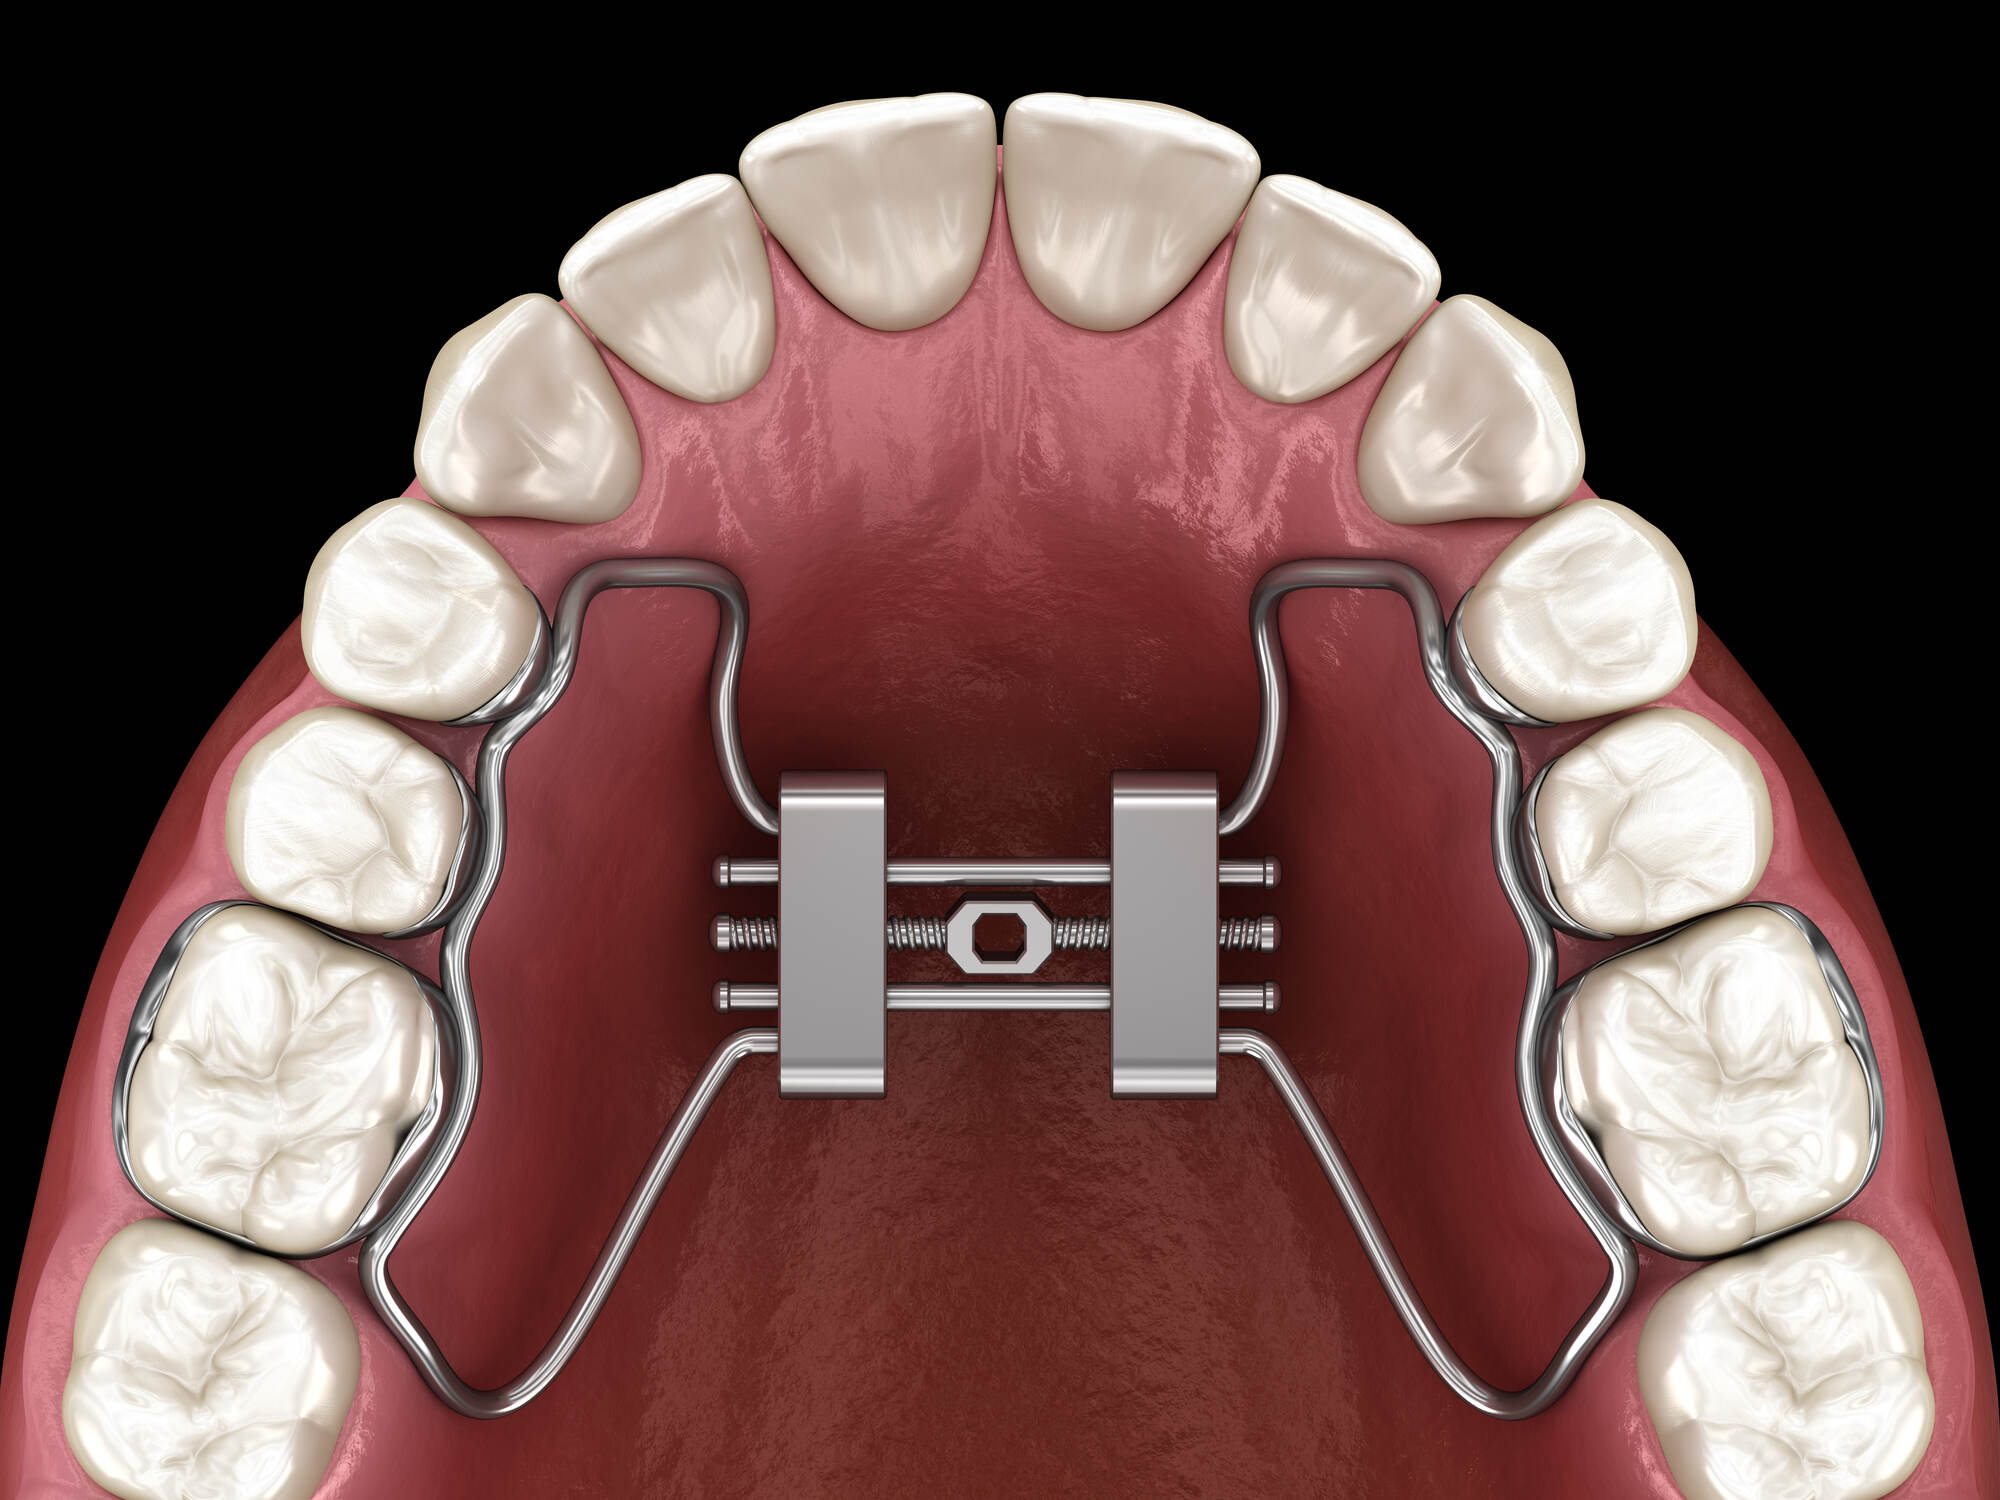

What Is a Palatal Expander?

A palatal expander is a custom-made appliance that fits in the roof of the mouth. It works by applying gentle pressure over time to gradually widen the upper jaw. The process is slow and controlled, allowing the bone to adapt safely.